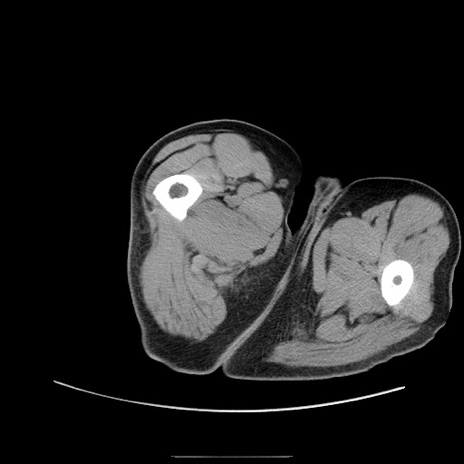

症例22(横断像)

【症例】50歳代男性

【主訴】腹痛

【現病歴】AVMからの被殻出血のため回復期リハ病棟入院中。 本日午後3時頃急に下腹部痛が出現した。

【既往歴】AVM、被殻出血、虫垂炎、高血圧

【身体所見】意識晴明、左半身不全麻痺、会話の理解は良好、36.5°C、腹部:膨隆、全体に板状硬、下腹部正中に圧痛点あり、反跳痛-、筋性防御不明、右下腹部にope scar

【データ】WBC 9400、CRP 0.06